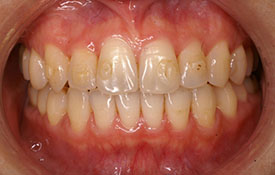

インビザラインの治療例:CASE-1

| プロフィール | 42歳 女性 |

|---|---|

| 所見 | 他院で行われた矯正歯科治療後の後戻りに悩まれて来院されました。 アイライナーの装着は、1日平均20時間ほどでした。 |